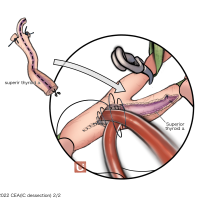

FEN2022シリーズ